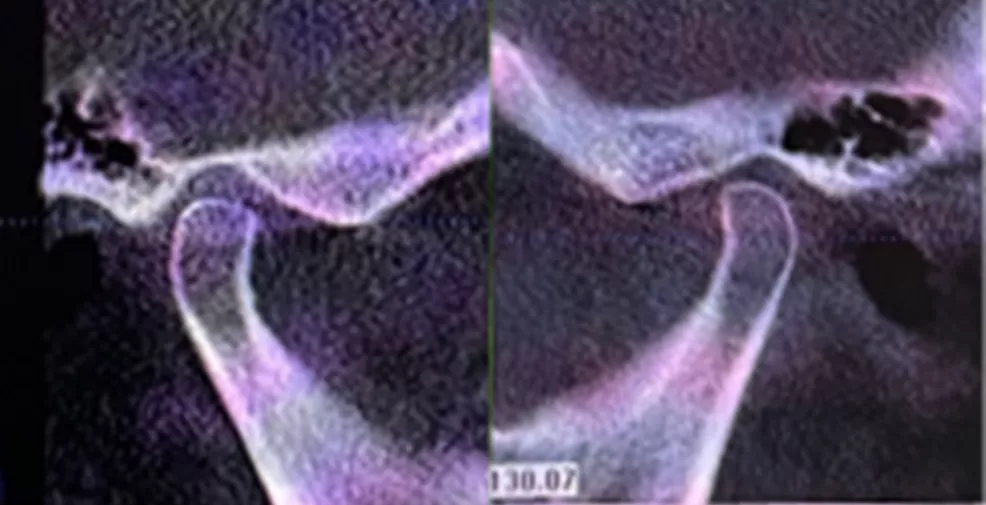

· 双侧髁突骨皮质连续。

· 修复体戴入后髁突位于关节窝内的适中位置。